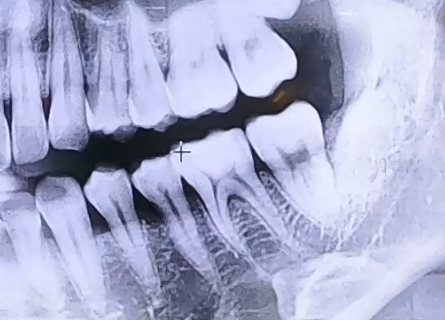

매복 사랑니 치료 사례

BEFORE

사랑니로 인한 극심한 통증으로 내원해 주신 환자분입니다.

검사를 진행해 보니 매복 사랑니를 갖고 계셨고, 이 사랑니 아래쪽으로

잇몸에 염증이 생겨 잇몸뼈들이 녹아내리고 있었는데요.

해당 부위의 잇몸이 전반적으로 약해져 있었기 때문에

사랑니 발치 후 그 앞쪽 어금니들의 상태도 주의깊게 살펴야 했습니다.

다행히도 어금니는 많이 흔들리지는 않는 상황이었으므로 사랑니를 발치하고,

약해진 잇몸뼈가 회복될 수 있도록 한 뒤 뼈의 높이를 올리고 보강해 주기 위한

뼈이식 치료를 함께 진행해 드렸습니다.